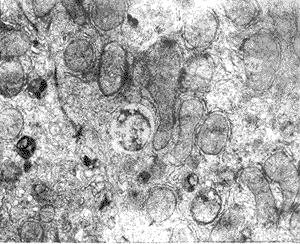

, http://www.100md.com 图1 对照组肝细胞内线粒体(M),纳虫泡内Sp结构完整,内含微线体(Mn)30000×

2.2.2 IL-6组 肝细胞内线粒体、内质网等丰富,线粒体嵴也清晰可见,相邻肝细胞质膜处有紧密连接结构,其交界处毛细胆管区附近可见一退变Sp,纳虫泡尚清楚,虫体空泡化 皱缩、结构不清(图2)。

图2 IL-6组肝细胞内Sp空泡化,线粒体(M)8000×

本文电镜观察结果表明,在Sp接种前静注4×104U IL-6,在鼠肝细胞内可见部分Sp发生退变,虫体显现空泡,皱缩,结构不清,这与Pied等观察到IL-6可抑制Sp在肝细胞内增殖,并对虫体造成形态学损伤以致溶解的结果是一致的[1],提示IL-6在Sp侵入和EEF发育的早期(Sp侵入后1h)即可造成对原虫的损伤。